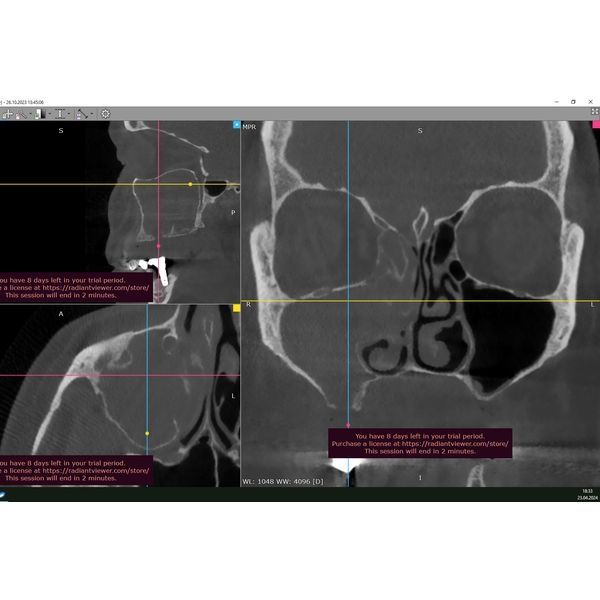

Была проведена конусно-лучевая томография головы. В ходе обследования определялись: обширный дефект мягких и твёрдых тканей верхней челюсти справа, тотальное затемнение верхнечелюстной пазухи (полное заполнение пазухи патологическим содержимым) с полипами и выделением содержимого в полость носа.